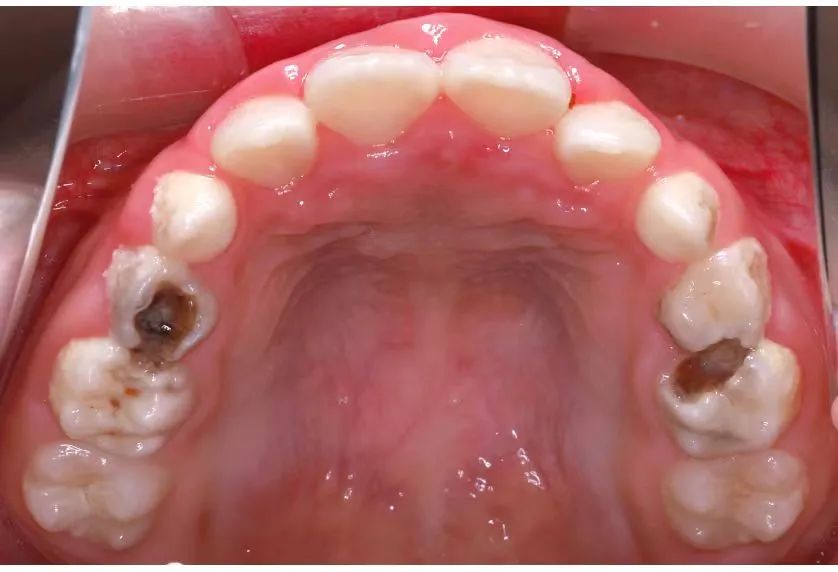

口呼吸使口腔长期处于相对干燥状态,容易引发嘴唇干燥、龋齿、牙龈红肿等口腔问题。

f0c214bf83f149153bff238022f36bdb.jpg